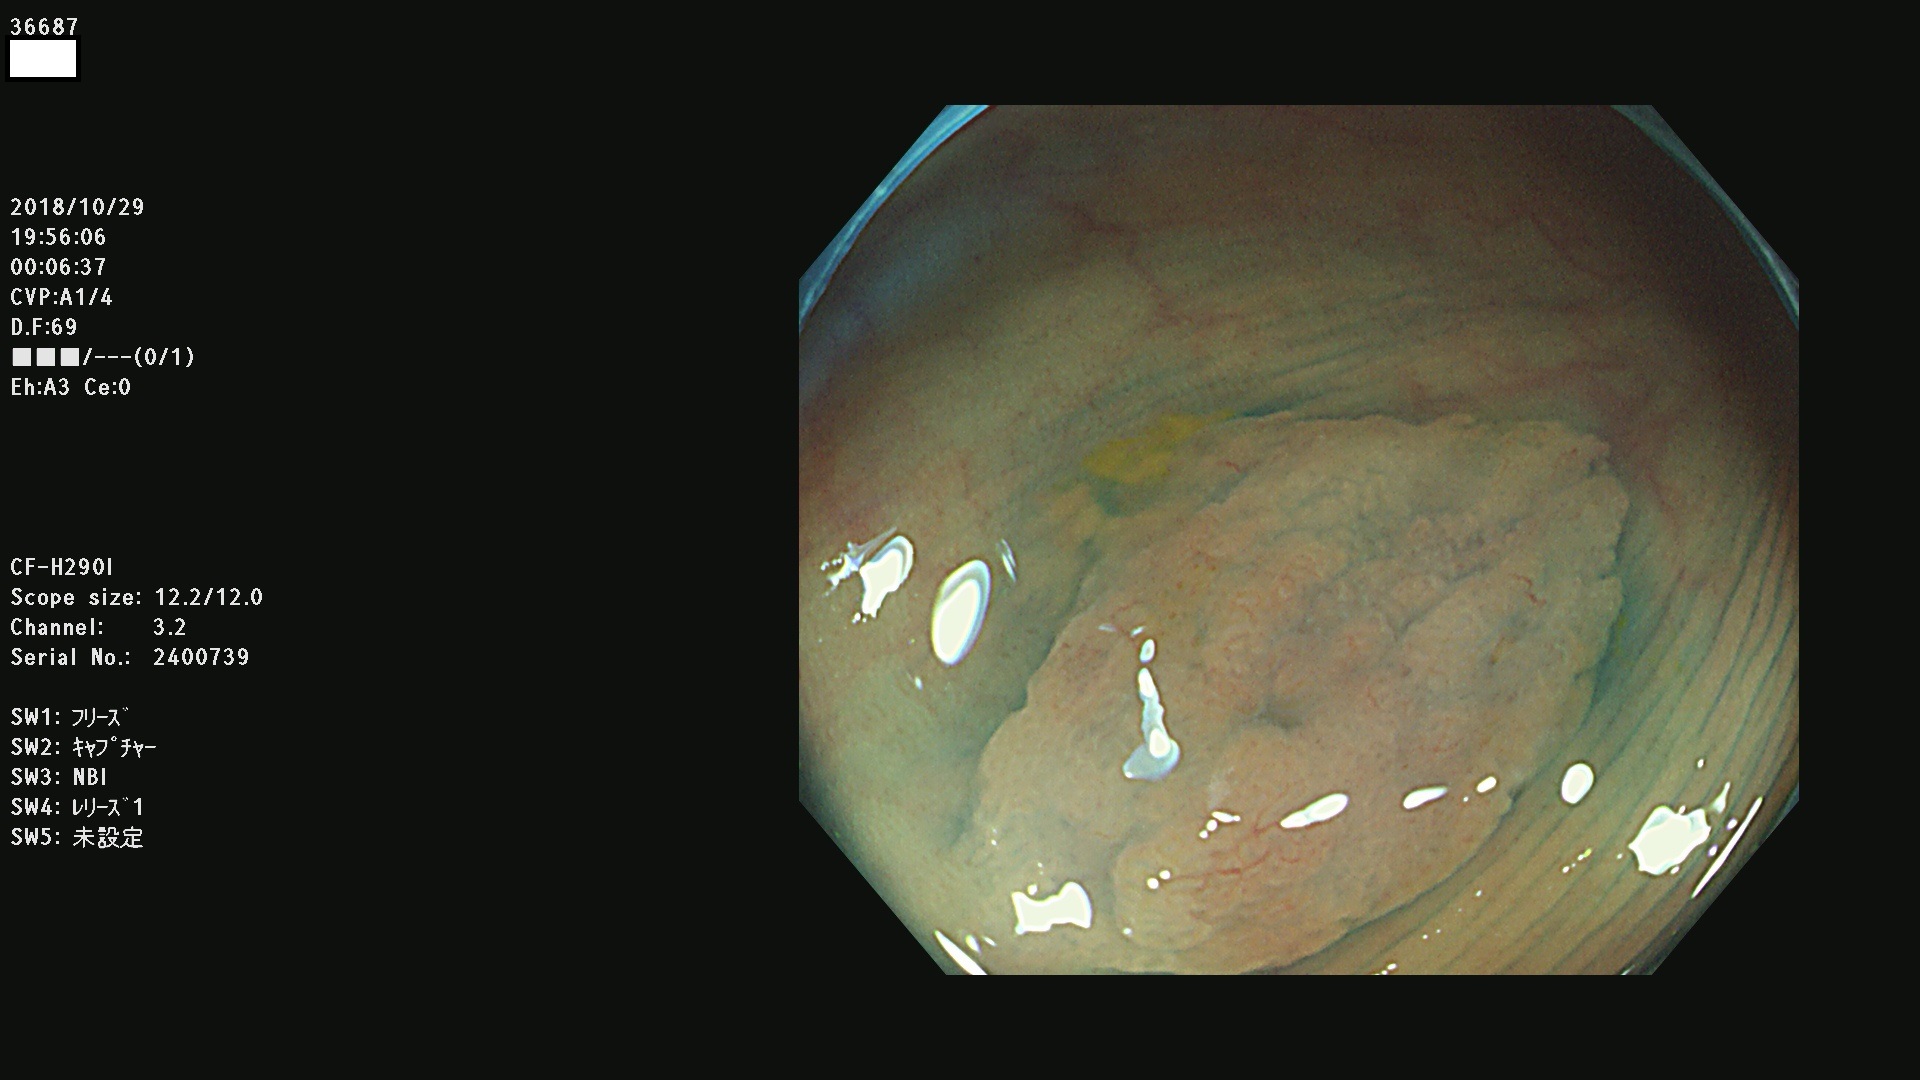

36600 36601 36603 36605 36606 36608 36609 36610 36611 36612 36613 36615 36617 36620 36621 36624 36625 36626 36627 36628 36629 36631(SSAPのみ) 36632 36633 36634 36636(SSAPのみ) 36637(SSAPのみ) 36639 36640 36642 36643 36644 36646 36647 36648 36649(SSAPのみ) 36650(SSAPのみ) 36652 36653 36654 36655(SSAPのみ) 36656 36657 36658 36659 36660 36661(SSAPのみ) 36665 36668 36669 36672 36673 36676 36677 36678 36679 36681 36682 36683 36684 36685 36687(SSAPのみ) 36691 36692 36693 36694 36695 36696 36697 36699(SSAPのみ)

発見困難で危険性の高い平坦型病変(上記100名より抽出)